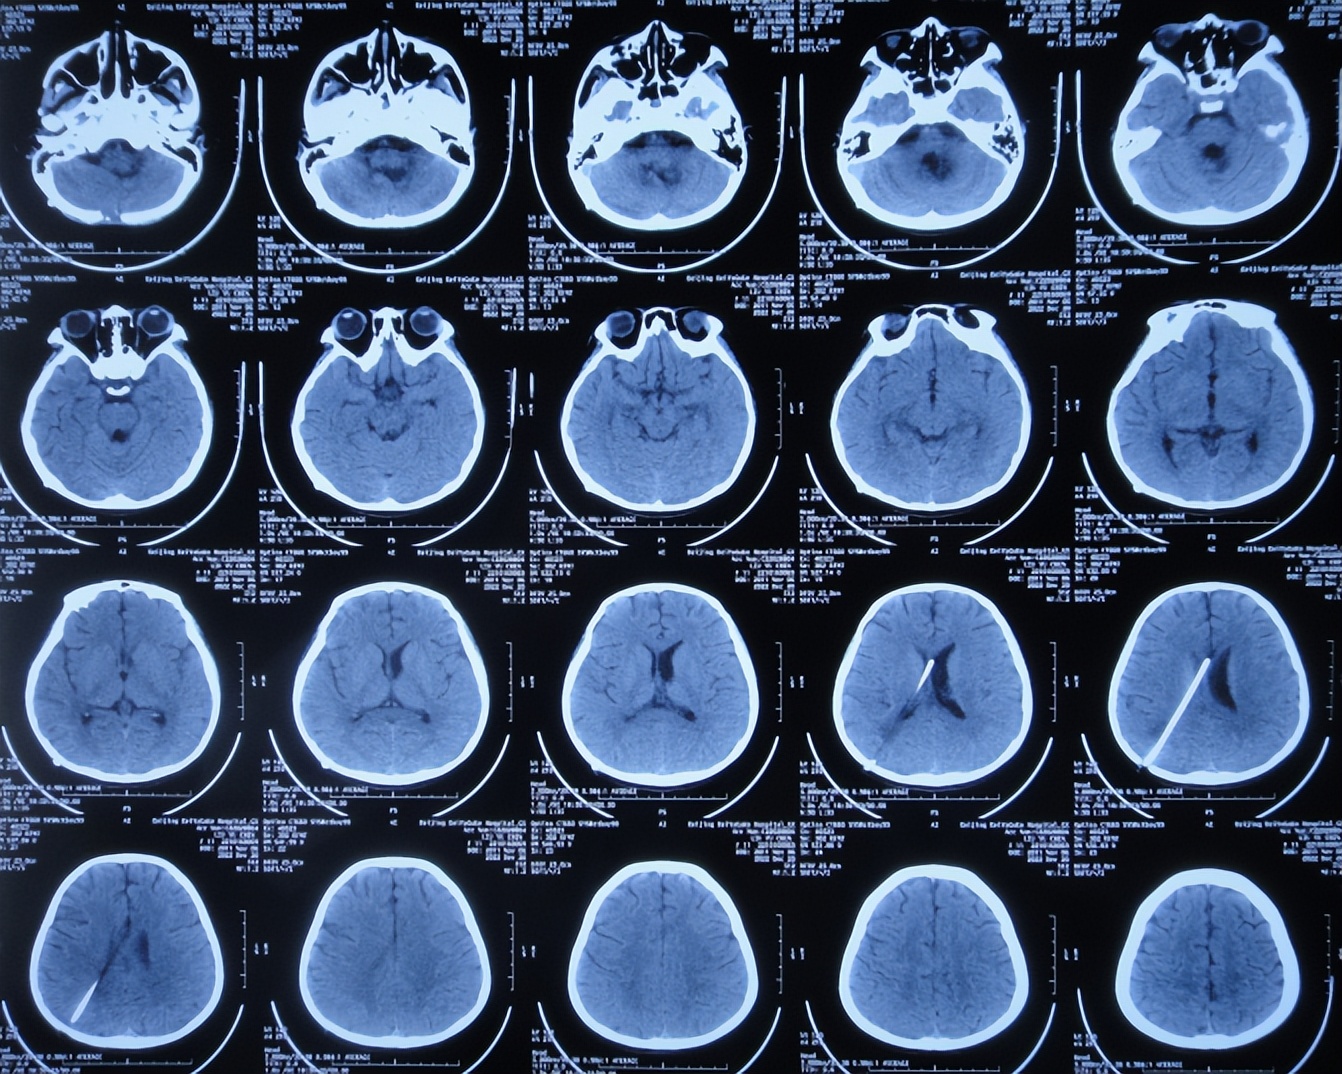

患儿于2022年10月10日,无诱因出现颈部疼痛,伴恶心呕吐、精神差,当时意识清楚,没有就诊,5天后即2022年10月16日,凌晨再次出现恶心呕吐多次,精神差,变得嗜睡,能被叫醒,就诊于山西省大同市浑源县某医院,查颅脑CT( 图-1 )示“小脑出血”,给予止血对症治疗。

图-1: 2022年10月16日颅脑CT上午11点

2022年10月16日(小脑出血当天晚上)住入李小勇脑脊液科。入院时:嗜睡,能被叫醒;时有恶心呕吐( 图-2 )。查头颅CT示小脑出血,脑室有扩张( 图-3 );肺部感染( 图-4 )。

图-3: 入院时颅脑CT晚上8点